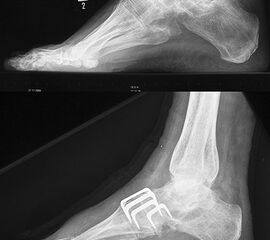

Lateralisierende Calcaneus-Osteotomie (Abb. 2 und 3, Video 2)

Die lateralisierende Calcaneus-Osteotomie ist ein Standard-Operationsschritt bei fast jeder Hohlfuβkorrektur. Der biomechanische Effekt der Osteotomie ist eine Verschiebung des Fersenkontaktpunktes und damit der beim Rückfuβ varus medialisierten Belastungsachse durch das OSG nach lateral. Diese statische Rückfuβ-Korrektur allein ist in der Lage, den bei Pes cavovarus anteromedial erhöhten OSG-Druck, der sehr wahrscheinlich zur korrespondierenden Arthrose führt, zu neutralisieren 7. Zuklappende Osteotomien mit Entnahme eines lateralen Knochenkeils haben sich dabei weniger effektiv gezeigt als solche mit Lateralisation des Tubers. Mit der Lateralisation des Achilles-Ansatzes verringert sich die Inversionskraft der Sehne zugunsten der schwachen Eversion, wodurch gleichzeitig die Prädisposition für Supinationstraumata reduziert wird. Neben der klassischen Dwyer-Osteotomie (Entnahme eines lateralen, vertikalen Keils 8 haben sich vor allem die technisch einfache Verschiebe-Osteotomien („sliding osteotomy“) und die Z-förmigen Osteotomien (Pisani 1993, Malerba 9) mit Entnahme eines lateralen Keils aus dem horizontalen Anteil der Osteotomie aber ohne Lateralisation des Tuberfragmentes, sowie die Korrektur nach Hintermann (Knupp 2008) mit zusätzlicher Lateralisation des Tuberfragmentes) durchgesetzt. Bei neutral aligniertem OSG ist keine supramalleoläre Tibia-Osteotomie zur Korrektur des Rückfuβ varus indiziert. Generell sollten Osteotomien gegenüber korrigierenden Arthrodesen der Vorzug gegeben werden. Die im Folgenden beschriebene Verschiebeosteotomie ist technisch einfach und hinsichtlich OSG-Druckneutralisation ebenso effektiv wie die Z-Osteotomien 7.

• Kontrolle der korrekten Schraubenlage im BV (Abb. 3).